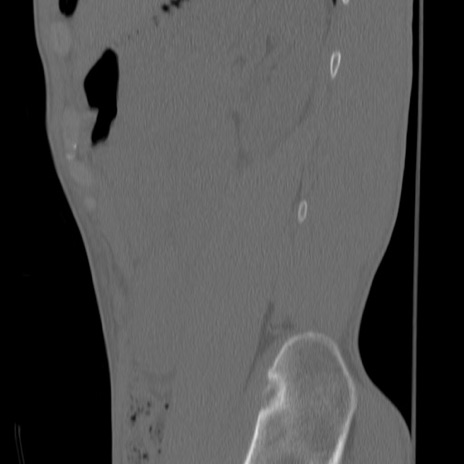

症例3 腰椎CT(矢状断像)

【症例】30歳代男性

【主訴】腰痛

【現病歴】本日旅行先で観光中に、友人と衝突し転倒し受傷。

【身体所見】麻痺なし、右下腿内側前面外側、左下腿内側に知覚鈍麻・しびれ

異常所見と診断は?

腰椎CT